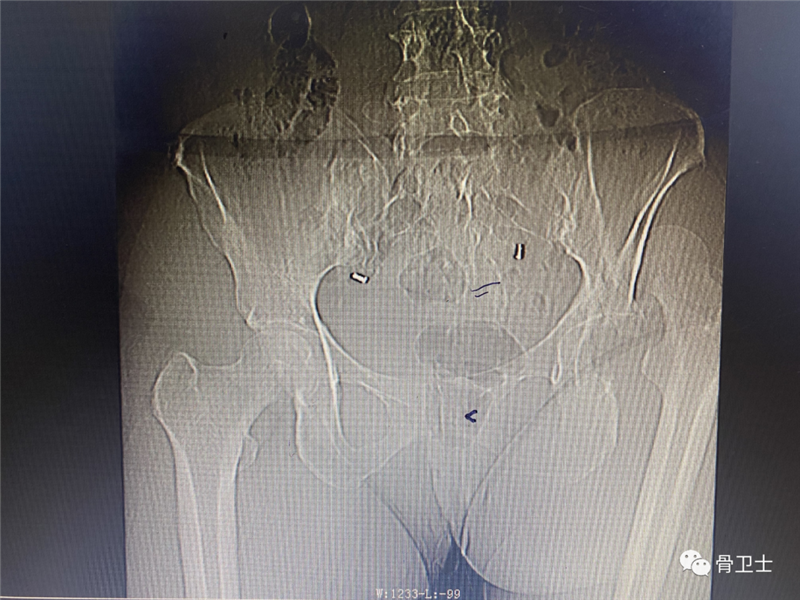

辅助检查:完善血型0型,Rh(D)血型阳性。2月22日,血常规示白细胞15.11X10^9/L、中性细胞比率90.51%,血象偏高,考虑创伤后体内应激反应所致;电解质常规检查:钾5.74mmol/L,嘱其低钾饮食,择期复查;肝功能常规:谷草转氨酶65U/L,考虑创伤所致,择期复查;血糖11. 82mmol/L,为餐后血糖,实属正常。新冠肺炎检查、肾功能示未见明显异常。心电图示窦性心动过速,电轴正常;头颅+胸部CT示未见明显外伤性异常;左髋关节正侧位片+左膝关节正侧位片示左髋臼粉碎性骨折,左股骨头脱位;左髋关节正侧位片+左膝关节正侧位片示左髋臼粉碎性骨折,左股骨头脱位;CT成套:双髋关节(CT重建):左侧可见粉碎性骨折、股骨头后脱位。

▲X光片